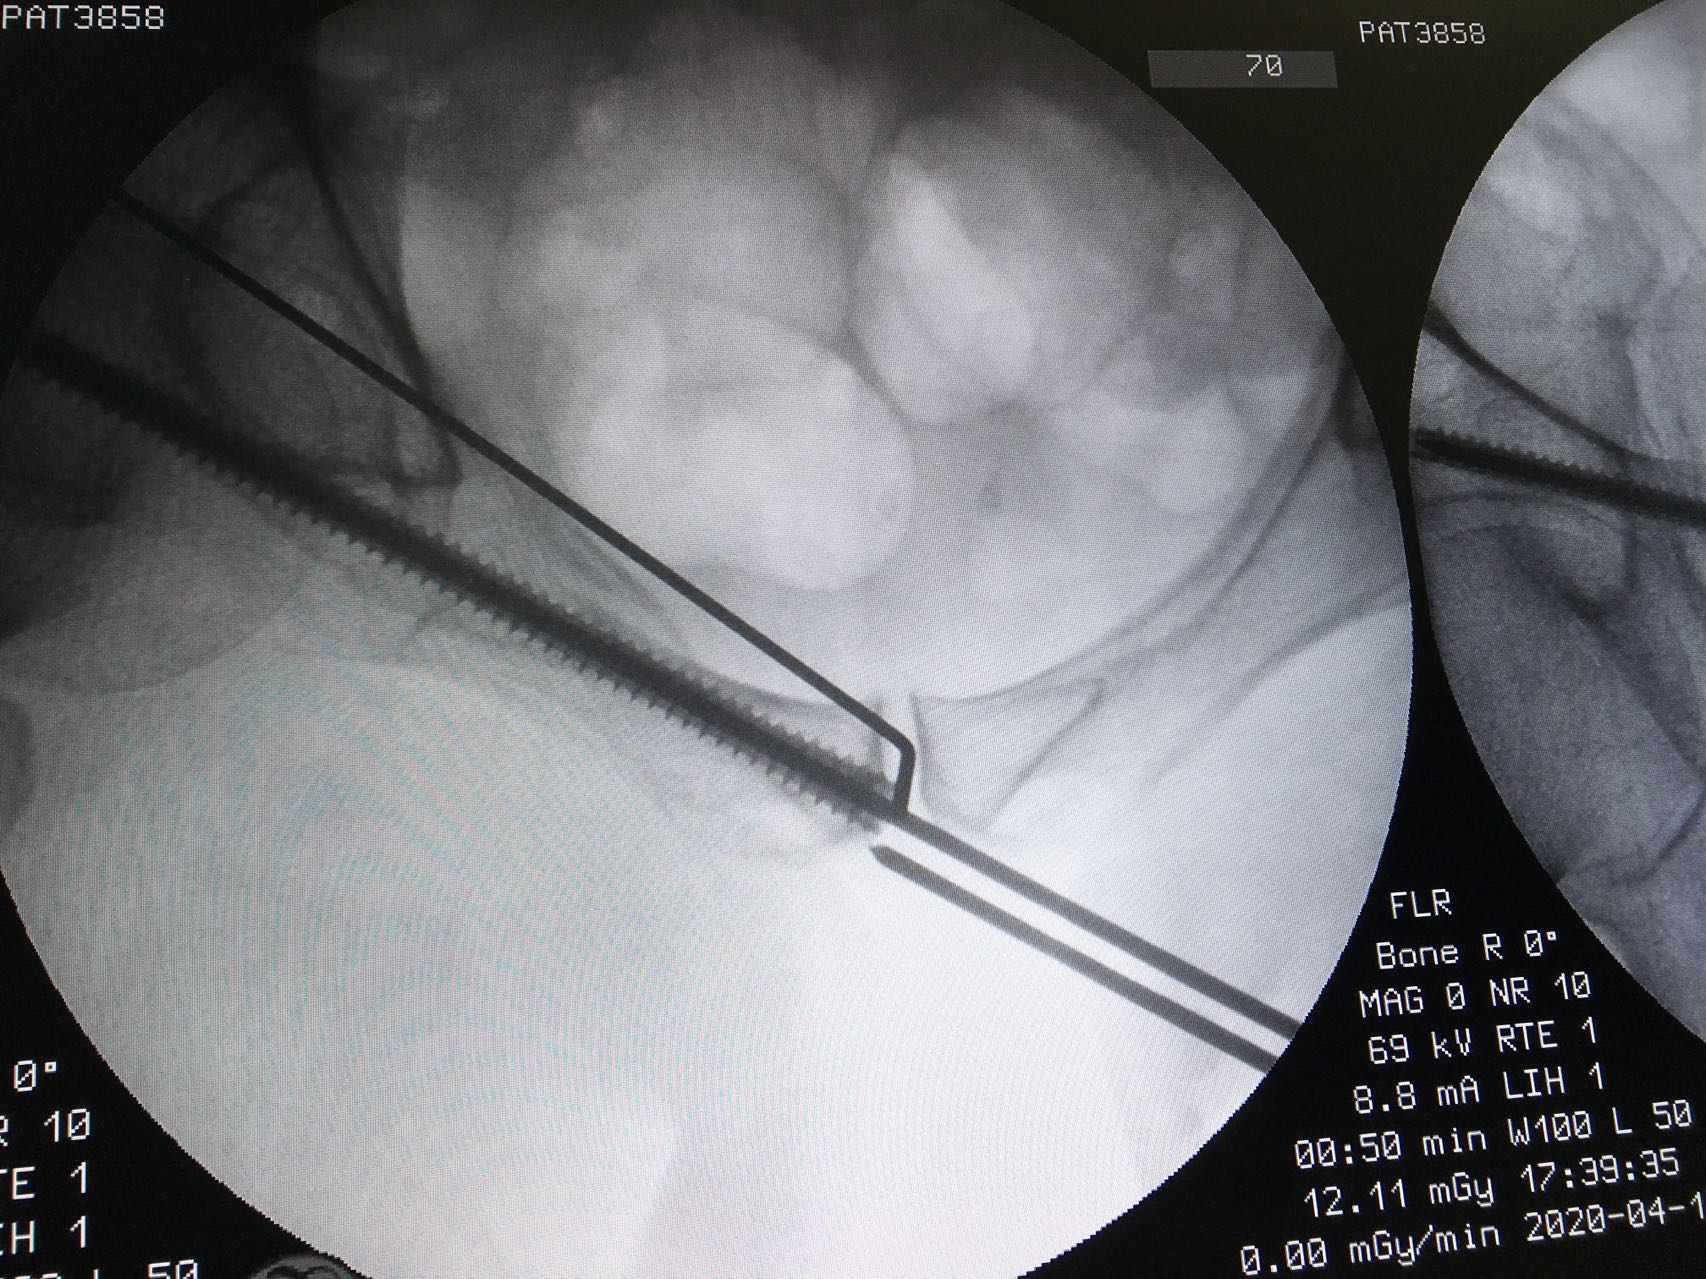

备皮,消毒,摆好透视机器,反复透视,确定最佳的进针点,确定最佳进针方向,一点不能马虎。因为进针的路很窄,旁边也都是重要的人体结构。

骨盆入口位

导针在位

骨盆出口位

进针点很好

螺钉位于骨性通道内